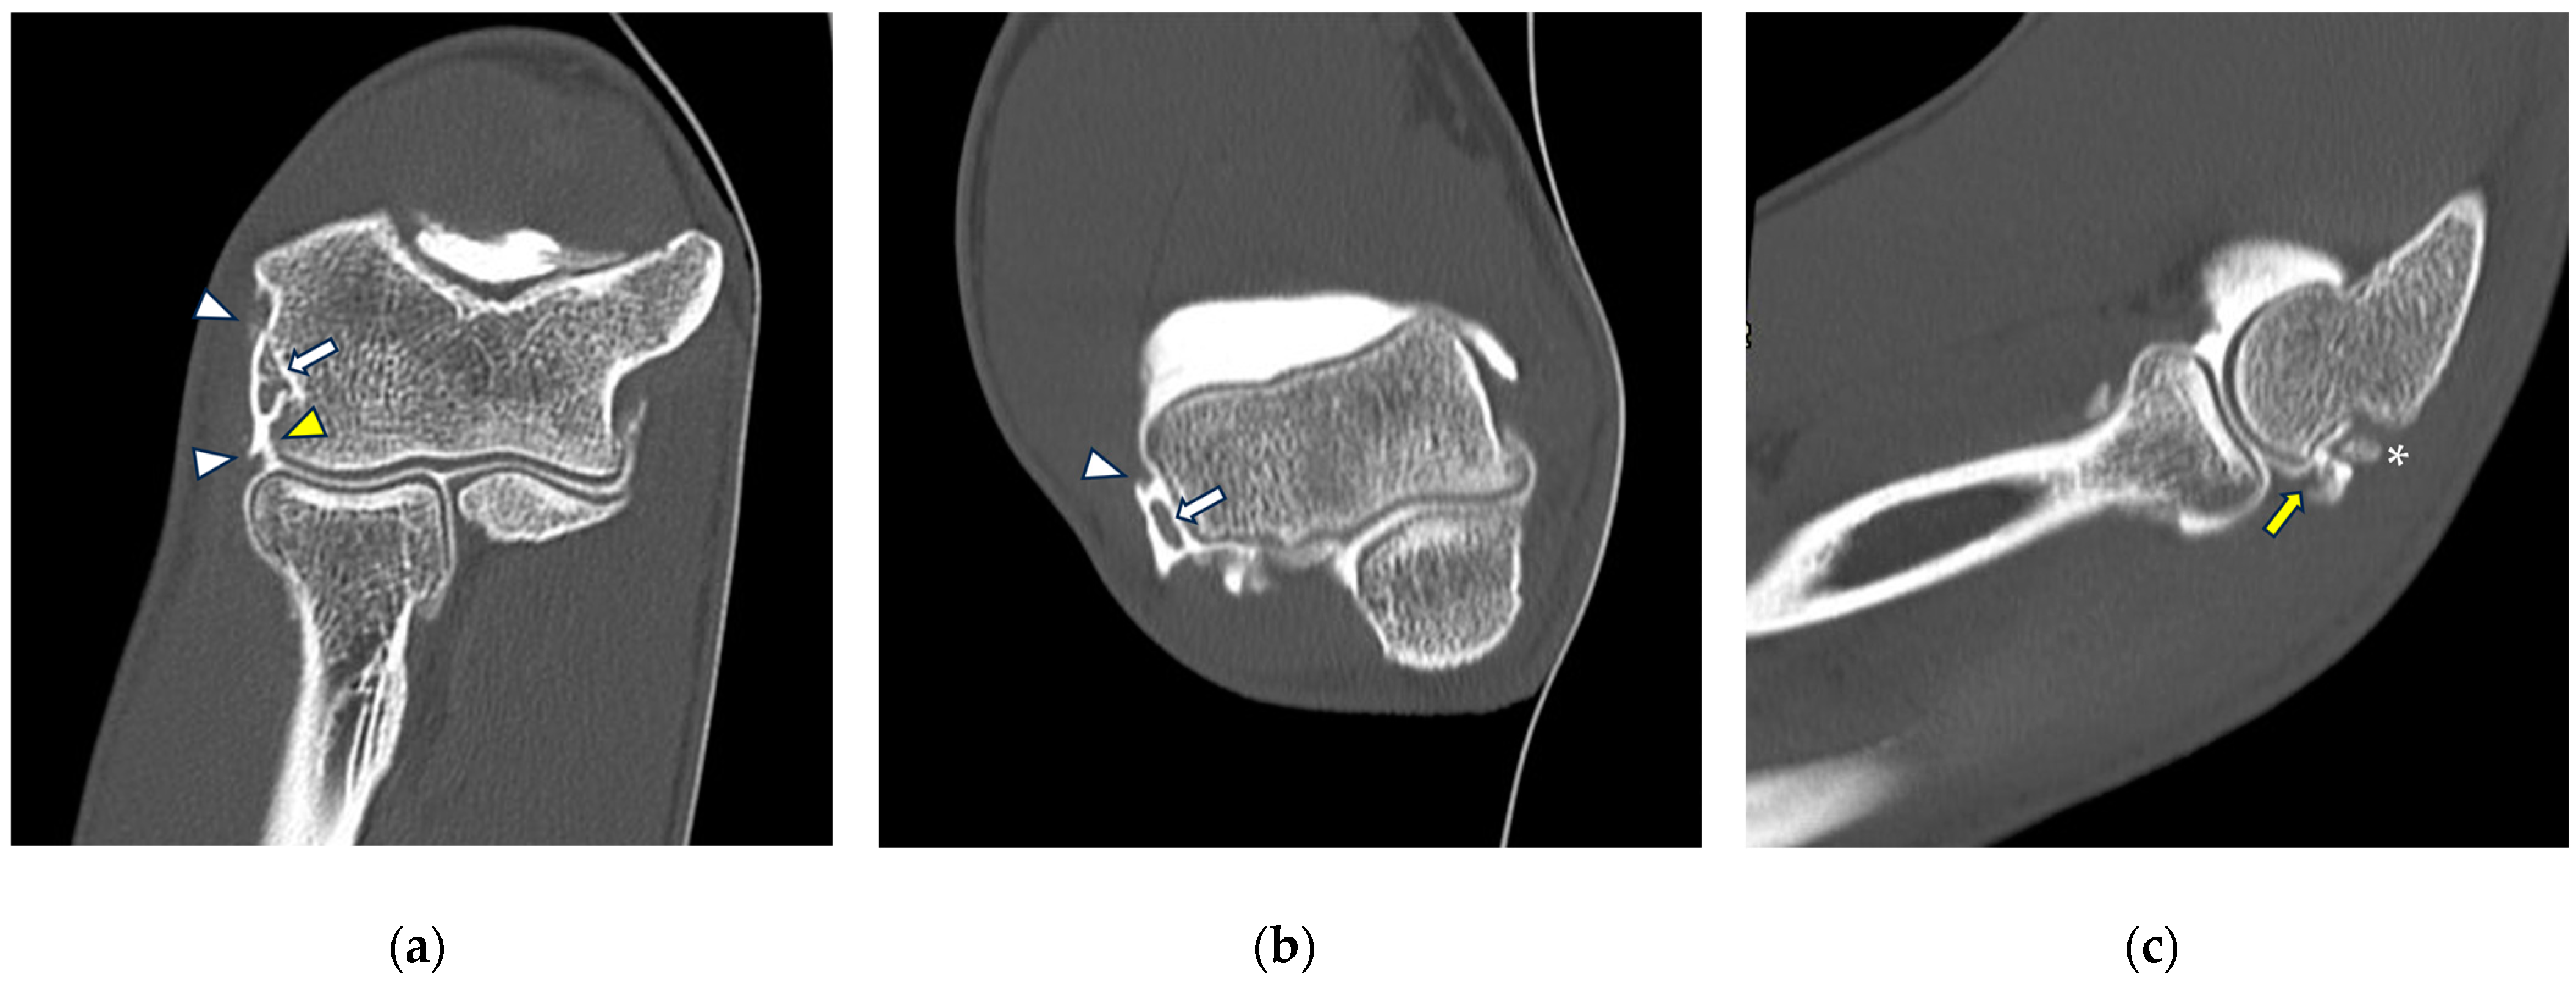

Figure 3.

CT arthrography of a patient with chronic elbow instability. (a) Sagittal image shows pitting and fissuring of radial head cartilage, involving >50% of its thickness (grade III) (white arrows); (b) coronal reformat of the same patient shows a focal full-thickness cartilage defect of the anteromedial radial head (grade IV) (white arrow). In the same image, mature calcifications can be seen at the insertion of the common extensor tendon (white arrowhead).